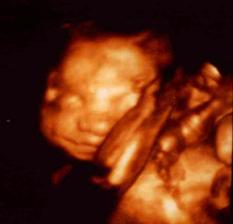

Že by se i na nás usmálo štěstí? 🙂

Je to už déle jak týden, co jsem si dělala test a našla jsem na něm dvě neskutečně tlusté čáry, značící těhotenství.... K lékaři jdu až 15.11.2010, abych si nechala tuto úžasnou novinku potvrdit (dřív to bohužel nejde).